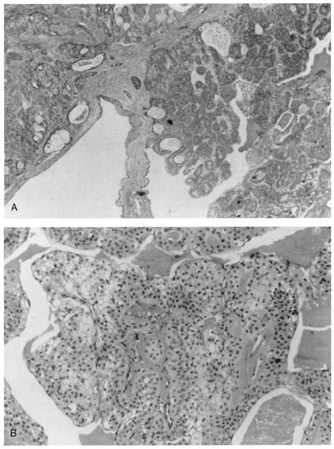

Dermoid cysts are usually present at birth and commonly occur around the eyes. They may be adherent to the periosteum. Dermoid cysts are believed to result from sequestration of skin and its appendages along embryonic lines of closure and, thus, are commonly found at the frontozygomatic suture.

Histologically, dermoid cysts are lined by epidermis possessing various mature appendageal structures (Fig. 22). These include hair follicles with terminal hairs, sebaceous glands, eccrine glands, and, occasionally, apocrine glands.

Fig. 22. A. Dermoid cyst shows hair follicle (h) and hair shaft (arrows) in cyst lumen. B. Dermoid cyst has skin appendages in cyst wall (arrow), is lined by stratified squamous epithelium, and contains desquamated keratin in its lumen (L). There is a granulomatous inflammatory infiltrate (g) due to rupture of cyst. (From Yanoff M, Fine BS: Ocular Pathology, 3rd ed. Philadelphia, JB Lippincott, 1989, 186.)